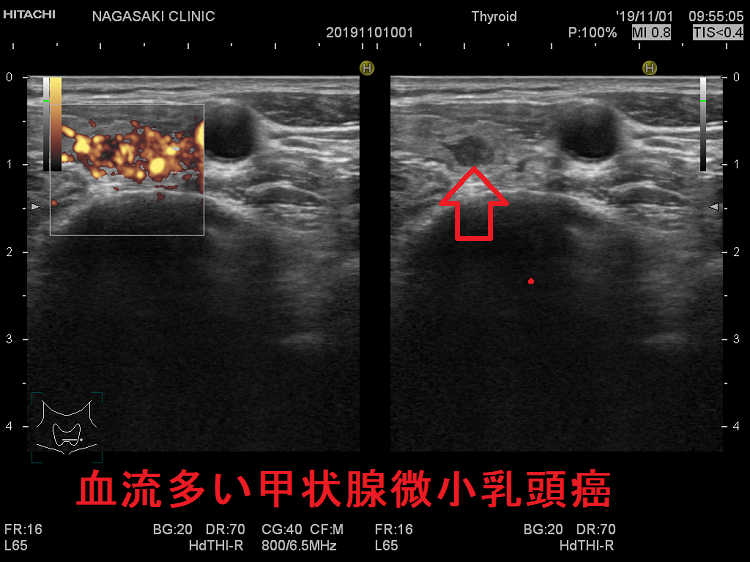

血流多い甲状腺微小乳頭癌

甲状腺乳頭癌に特徴的な微細石灰化を持たない甲状腺微小乳頭癌は進行しやすいとのことです。石灰化は同じ場所に長く留まらねば起こりません、微細石灰化を持たない甲状腺微小乳頭癌は短期間で成長していると推察されます。